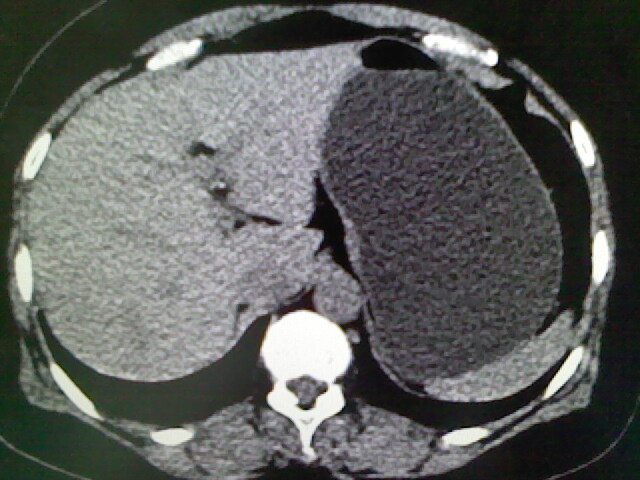

以下是引用卜一在2009-4-2 13:26:00的发言:[br]胆囊颈部结石伴胆囊炎!另:建议增强,待除外肝内占位及胆囊占位!

以下是引用liaoqiang在2009-4-2 16:23:00的发言:[br]胆囊是否切除?胆囊颈区致密影考虑金属夹?结石?肝脏右叶低密度影,考虑增强。